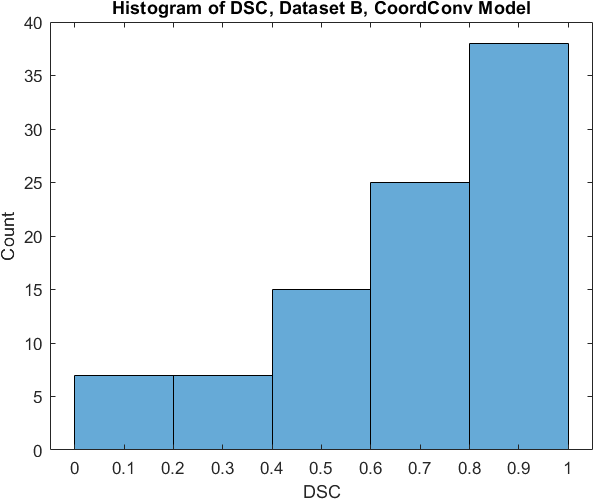

Qualitative prediction results of the two proposed models (baseline nnU-Net and nnU-Net with coordinate convolutions) on the two datasets are shown in Figure 2. Tables 1 and 2 summarise the quantitative performances in terms of DSC and area statistics. Histograms of the DSC values are shown in Figure 3. The median DSCs between the manual segmentations on the subsets of 10 images (i.e. the estimates of inter-observer variability) are also shown in Table 1.

It can be seen that, despite having fewer images, the baseline model for Dataset A obtained a higher median DSC than the model for Dataset B. For Dataset A the coordinate convolution model improved the DSC and reduced the area error and bias. In two-tailed Wilcoxon signed rank tests (0.05 significance) the difference between the baseline DSC and that of the coordinate convolution model was found to be statistically significant for Dataset A () but there was no statistically significant difference for Dataset B (). Interestingly, for both Dataset A and Dataset B, both the baseline and coordinate convolution models performed better than the estimate of inter-observer variability. However, we note that the inter-observer variability is quite high (i.e. median DSCs of 0.78 and 0.71), likely reflecting the difficulty and partly subjective nature of the effusion segmentation task. Therefore, it seems likely that the deep learning models are learning to segment effusion in the style of the main observer, which may not always be consistent with the second observer. In addition, the histograms shown in Figure 3 suggest that there are a significant number of failure cases in the outputs of both models (although fewer for the coordinate convolution model for Dataset A), again reflecting the difficulty of the task.